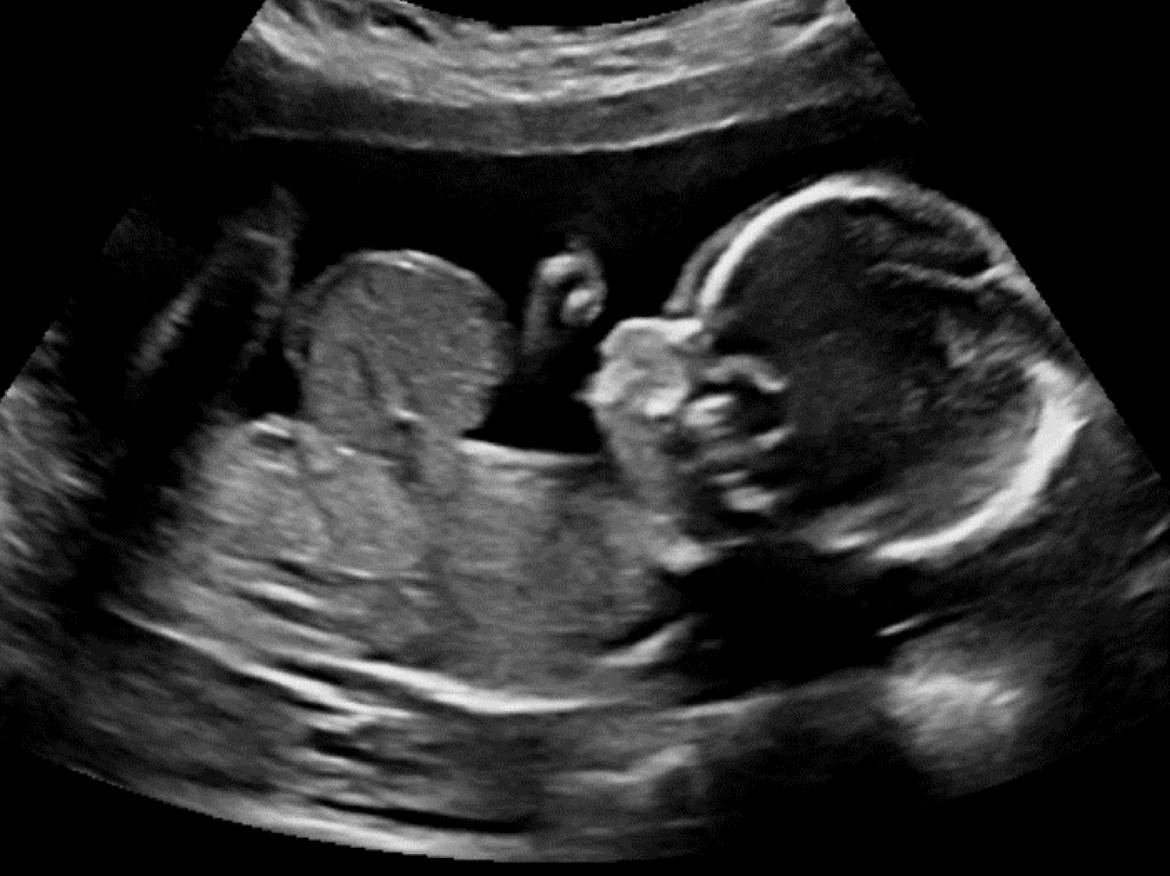

Wenn bei Dr. med. Sabine Grasshoff-Derr das Telefon klingelt, sind es nicht selten die Kolleg:innen aus dem Pränatalzentrum, die soeben Eltern eine beunruhigende Diagnose überbringen mussten. Sie bitten die Chefärztin der Klinik für Neugeborenen-, Kinderchirurgie und -urologie, dazuzukommen und sich mittels Ultraschall ein eigenes Bild zu verschaffen. Denn wenn feststeht, dass ein ungeborenes Kind eine auffällige Entwicklung zeigt, braucht es eine frühzeitige Beurteilung verschiedener Spezialisten.

Auch bei Fehlbildungen an Nieren oder Harnröhren muss so zeitig wie möglich eine Entlastung geschaffen werden. Zum Beispiel bei Kindern mit angeborenen Harnröhrenklappen, die unterhalb der Blase das Abfließen des Urins verhindern. Blase, Harnleiter und Nieren sind dann gestaut und die Nieren können dauerhaft geschädigt werden. Nicht selten werden die Kinder deswegen sogar dialysepflichtig. Ist bereits in der Schwangerschaft im Ultraschall zu sehen, dass die Nieren durch eine solche Fehlbildung gestaut sind, wird manchmal noch vor der Geburt ein Stent über die fetale Bauchdecke eingesetzt, über den der Harn aus der Blase ins Fruchtwasser abgeleitet wird. Sind die Kinder auf der Welt, wird der Stent kinderchirurgisch entfernt und ein Katheter über die Bauchdecke in die Blase eingesetzt. Denn auch in diesem Fall kann die Fehlbildung nicht sofort behoben werden. Erst wenn die Kinder etwas größer sind, können diese sogenannten Urethralklappen über eine Blasenspiegelung geöffnet und entfernt werden. Bis dahin werden die Kinder in der Nephrologie des Clementine Kinderhospitals medizinisch betreut. In enger Abstimmung mit den dortigen Nephrologen wird entschieden, wann die urologische Operation am Bürgerhospital erfolgen soll.